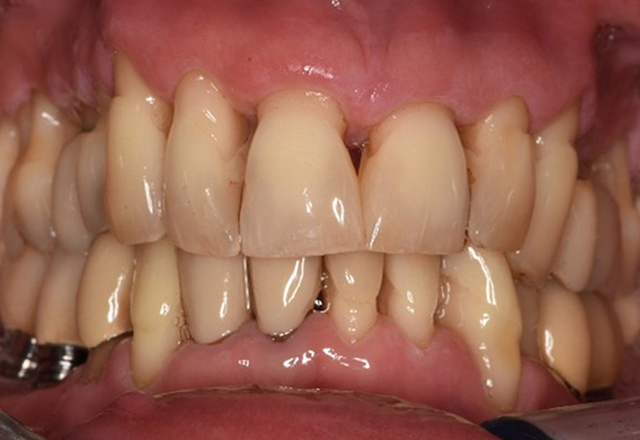

Fallpräsentation: Management komplexer Zahnprothetik

Es ist längst bekannt, dass Mundgesundheit und Allgemeingesundheit in direktem Zusammenhang stehen und einen zum Teil bidirektionalen Einfluss aufeinander haben. Die Berücksichtigung beider Faktoren sind bei der Planung der oralen Prävention und Therapie der Patienten in der Zahnarztpraxis unabdingbar. Dabei ist oberstes Ziel, die Gesundheit und die Lebensqualität der Patienten sowohl aus zahnmedizinischer -und medizinischer Sicht zu erhalten. mehr Infos